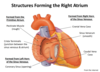

Describe the blood supply to the skin ?